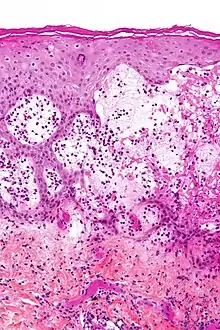

Pemphigoid gestationis (PG), also known as gestational pemphigoid, is an autoimmune variant of the skin disease bullous pemphigoid, that first appears in pregnancy.[3] Symptoms include blisters, small bumps, hives, and intense itching.[1] It usually starting around the belly button before spreading to the chest and limbs; with the head, face, and mouth being spared.[1][4] Onset is usually in mid-pregnancy to shortly after delivery.[1][5]

It is caused by antibodies against the mother's own skin, resulting in skin layers splitting and forming blisters.[4] It is possibly triggered by some placenta cells entering the mother's blood.[4] Risks include molar pregnancy and choriocarcinoma.[1] It does not spread between people and does not run in families.[4] It typically lasts six months and can reoccur in future pregnancies, menstrual periods, and from birth control pill.[1] In some people, it persists long-term.[1] Diagnosis is based on progression of symptoms, blood tests, and skin biopsy with immunofluorescence.[6][5] It can resemble pruritic urticarial papules and plaques of pregnancy (PUPP), erythema multiforme, drug reactions and blistering scabies.[1]

Pemphigoid gestationis is an autoimmune variant of the skin disease bullous pemphigoid, and first appears in pregnancy.[3]

Circulating complement-fixing IgG antibodies attach to the lamina lucida resulting in the skin layers splitting and forming blisters, possibly triggered by some placenta cells entering into the mother's blood.[1] The triggering antigen, transmembrane collagen XVII, is part of the baby's membrane cells that encourage the movement of placental cytotrophoblastic cells.[1] The disease appears to be triggered by female hormones.[1] It can recur in subsequent pregnancies, menstrual periods and oral contraceptive pill.[1] A molar pregnancy and choriocarcinoma can provoke it.[1]

Diagnosis is by its appearance and behaviour, blood test, biopsy and immunofluorescence.[6]